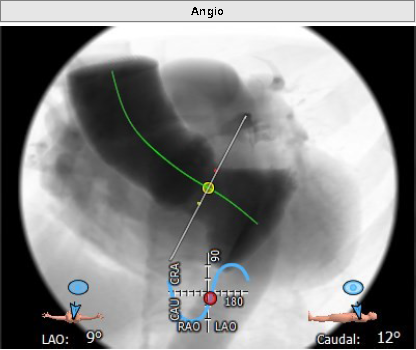

升主动脉增宽:42.6mm,最佳投射角度:LAO:9°Cranial:12°。

最佳投射角度:LAO:9°Cranial:12°,瓣环、瓣叶及窦部无明显钙化